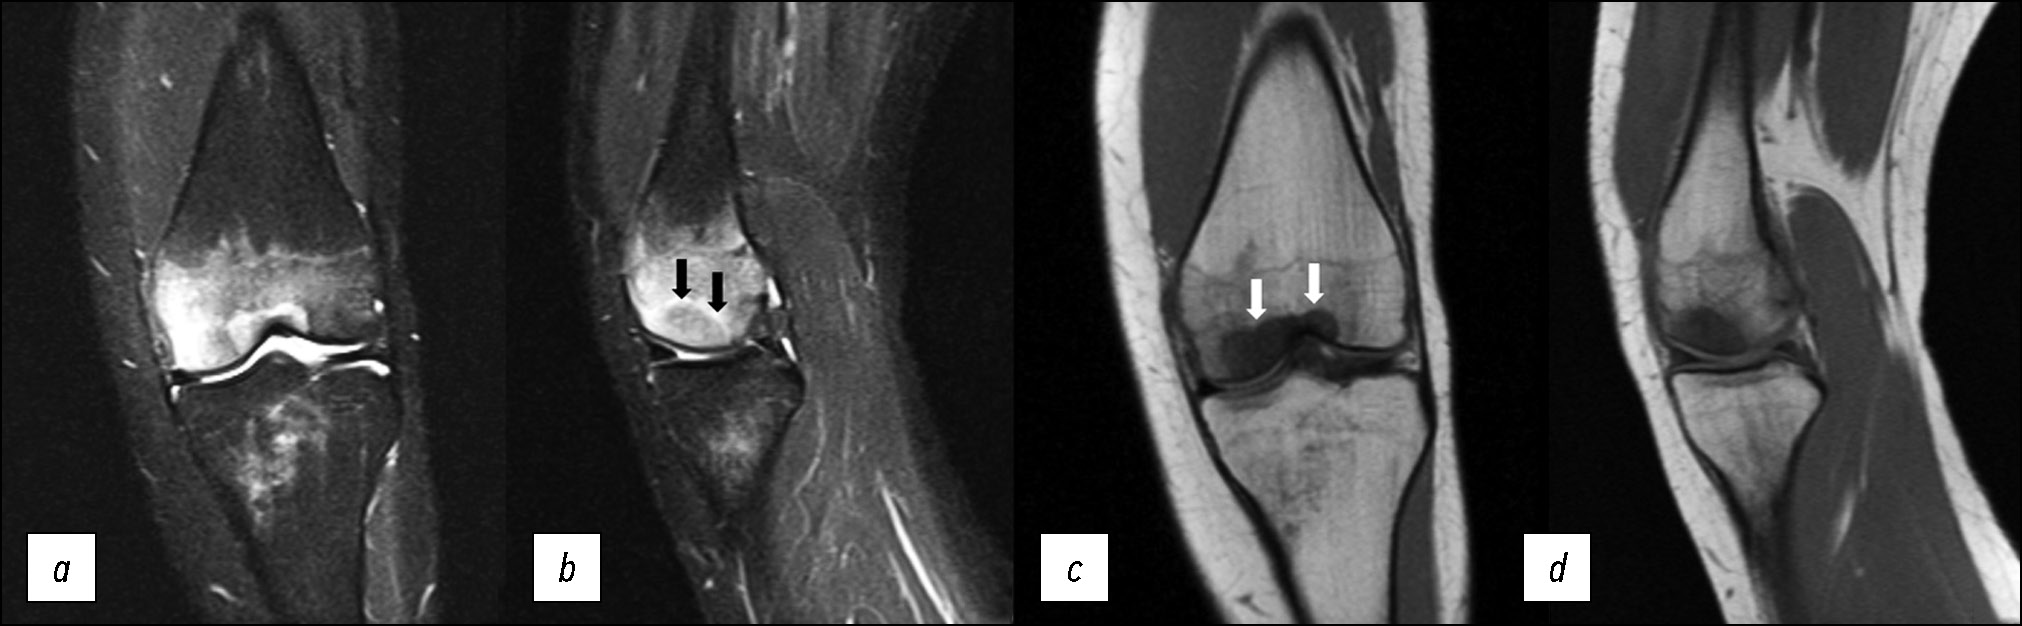

Пациентка Б., 35 лет, обратилась с жалобами на боль в правом коленном суставе, которая возникла после 4 дней регулярных пробежек по 5 км. На рентгенограммах коленного сустава патологии не выявлено. При МРТ-исследовании выявлен отёк в области внутреннего мыщелка большеберцовой кости, сочетающийся с зоной перелома между эпифизом и диафизом большеберцовой кости. Поставлен диагноз: стрессовый перелом проксимального отдела правой большеберцовой кости.

Особенностью отёка костной ткани при стрессовых переломах является наличие, как и при субхондральных переломах, искривлённой линии, которая является гипоинтенсивной на T1-взвешенных и PD-режимах с подавлением сигнала от жировой ткани, но локализуется линия перелома ближе к диафизарной зоне (рис. 3).

Рис. 3. МР-томограммы коленного сустава: а, b — корональная и сагиттальная проекции в режиме PD с подавлением сигнала от жировой ткани, c, d — корональная и сагиттальная проекции в режиме T1 при стрессовом переломе внутреннего мыщелка большеберцовой кости справа. Стрелкой отмечена линия перелома.

Fig. 3. MRI scans of the knee: а, b — coronal and sagittal views in to suppress the signal from adipose tissue, c, d — coronal and sagittal views in T1-weighted sequences with a stress fracture of the medial condyle of the tibia. The arrows mark the fracture line.

Данный вид перелома так же, как и в клиническом случае 2, возникает без предшествующей травмы, локализуется в области мыщелков бедренной или большеберцовой кости. В отличие от субхондрального перелома, стрессовый перелом возникает при нормальной плотности костной ткани на фоне регулярных повышенных нагрузок (например, регулярный бег или марш). В зарубежной литературе описан как усталостный, или стрессовый, перелом — fatigue (stress) fracture [12].